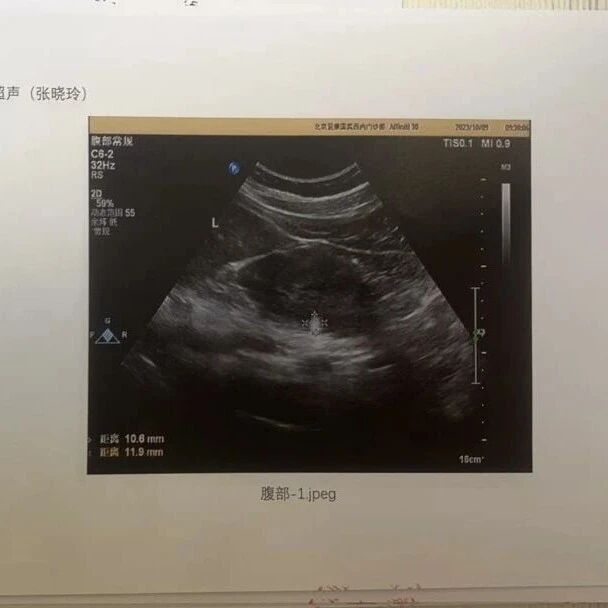

按照公开信息,2023年10月,张晓玲在爱康的体检报告中曾被提示“右肾钙化灶,左肾错构瘤可能”。对此,张晓玲在回应中称,自己有专门咨询爱康国宾的工作人员对体检报告作出解读,针对右侧肾脏“钙化灶”,医疗人员解读为“不需要任何处理,属于正常现象”。

在爱康集团7月18日的二次声明中,爱康集团称:“爱康经过内部医疗团队紧急调查及外聘专家的第三方核查,确认爱康在对张女士的肾脏的检查中,不存在漏诊或误诊情况,更不存在张女士所称‘假体检’。爱康完整保留了张女士肾脏超声检查的影像图片文件,只要张女士同意,爱康可以马上公开张女士的超声检查影像图片,公开透明,接受医疗专业人士以及公众的审核。”